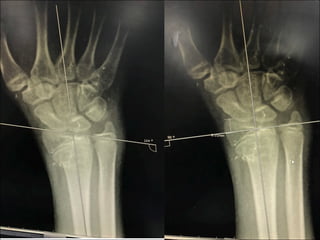

X-ray Right wrist

AP,Lateral

Impression

• Right wrist

• Close fracture

• Extra articular

• Anterior displacement

• Volar tilt

• Radial inclination 14˚

• Radial height 8mm

• Salter-Harries type 2

• Fernandez type 2